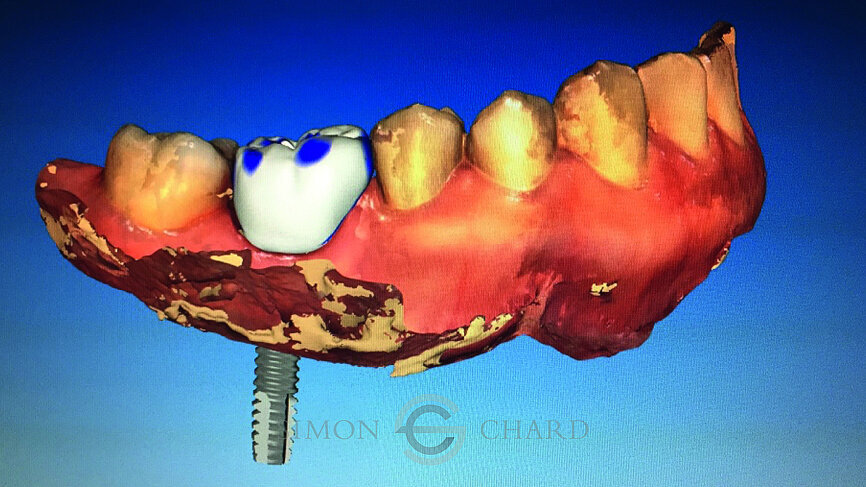

Following digital intraoral scanning (DIOS) of the opposing arch, working arch and buccal bite, a digital design was created using the biogeneric individual design mode. In this design mode on the CEREC Omnicam, the software evaluates the other teeth captured in the DIOS and tries to recreate what it believes to be the closest match to the original missing tooth (Figs. 9–11).

This tooth design is then positioned digitally within an e.max meso block. This meso block has a predetermined hole within it that acts as the access hole for the screw-retained crown, as well as the orifice into which a TiBase will be bonded (Fig. 12).